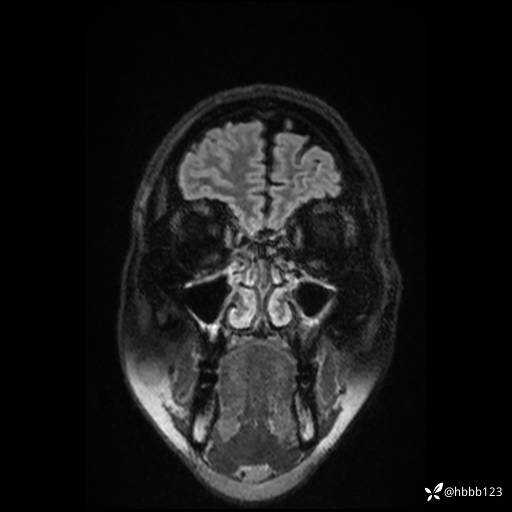

CUBE FLAIR横断位: